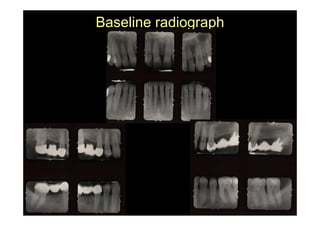

baseline

Baseline radiograph